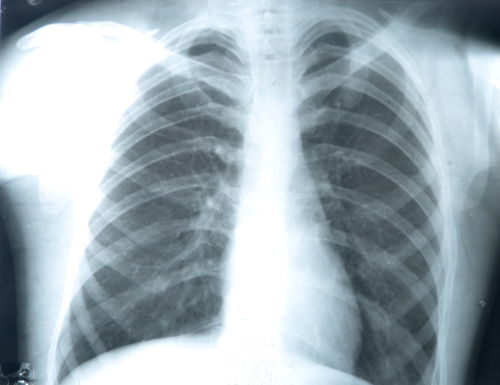

Raio X do tórax

O diagnóstico da síndrome de Boerhaave pode ser feito através de raio X do tórax e tomografia computadorizada, no entanto, é importante ter acesso ao histórico do paciente para excluir outras doenças com sintomas semelhantes, como perfuração de úlcera gástrica, infarto ou pancreatite aguda, que são mais comuns e que podem encobrir a síndrome.